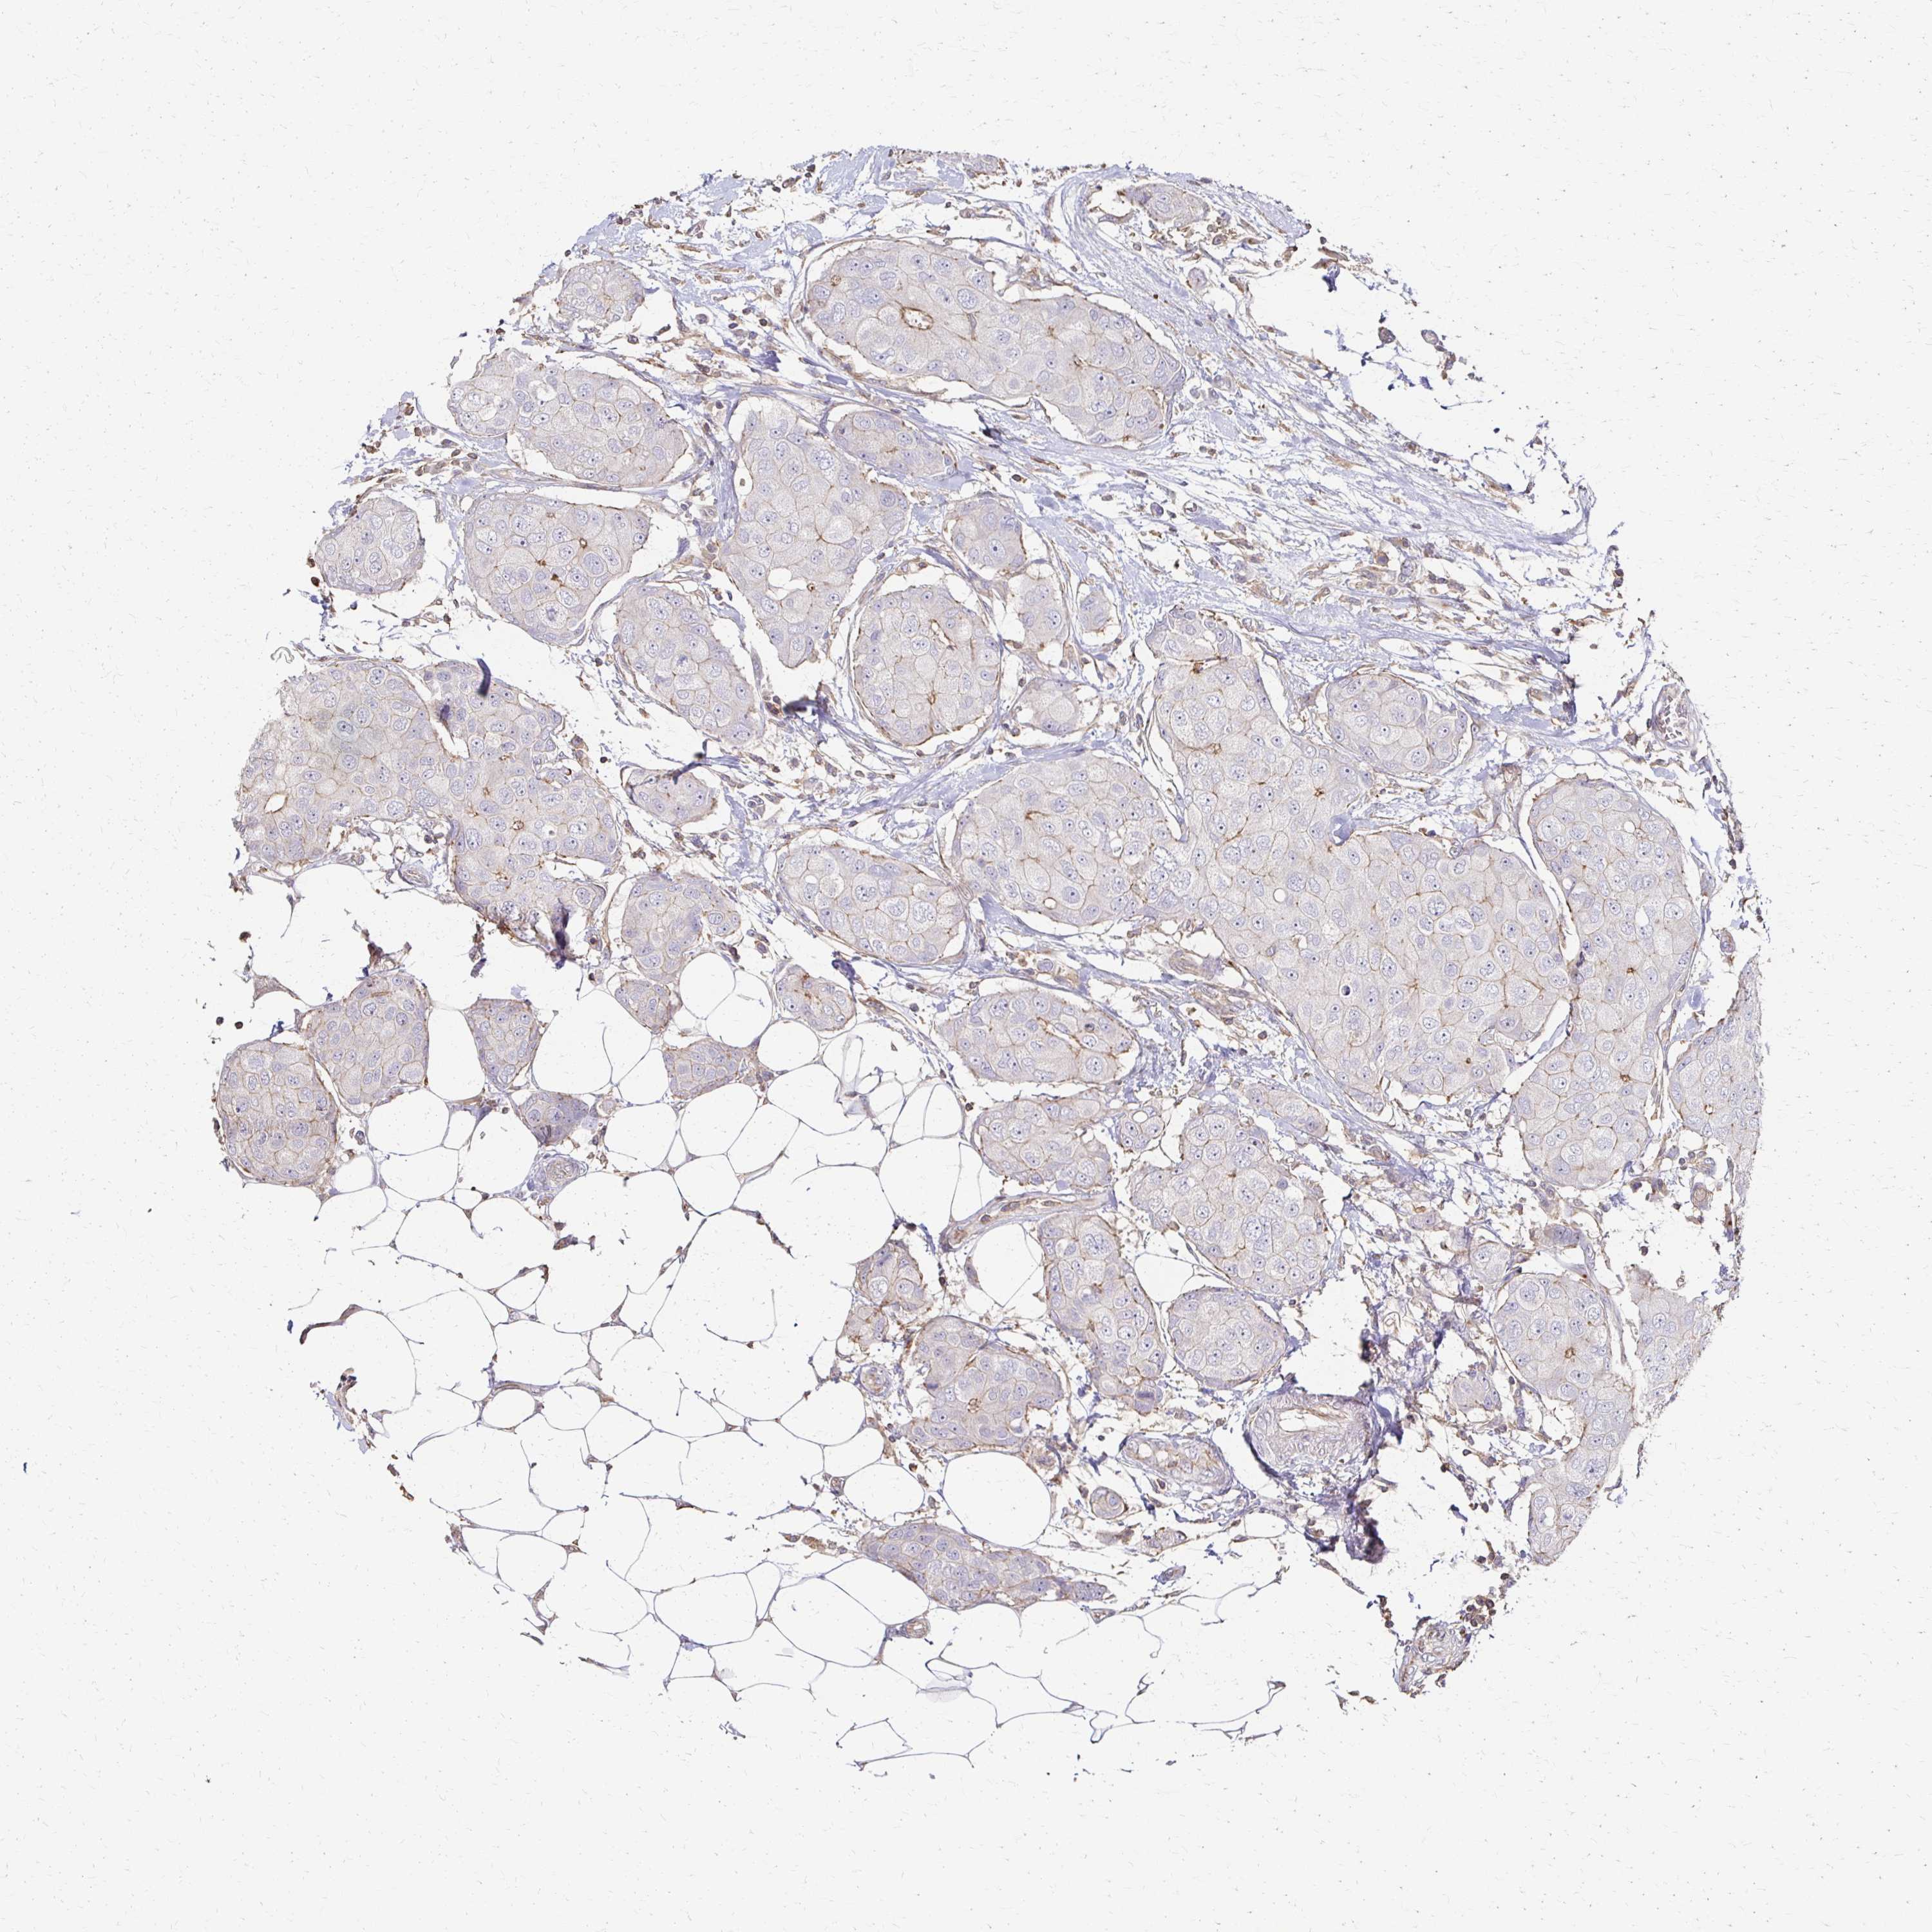

CANCER BREAST CANCER Show tissue menu

BRCA TCGA BRCA VALIDATION PROTEIN EXPRESSION